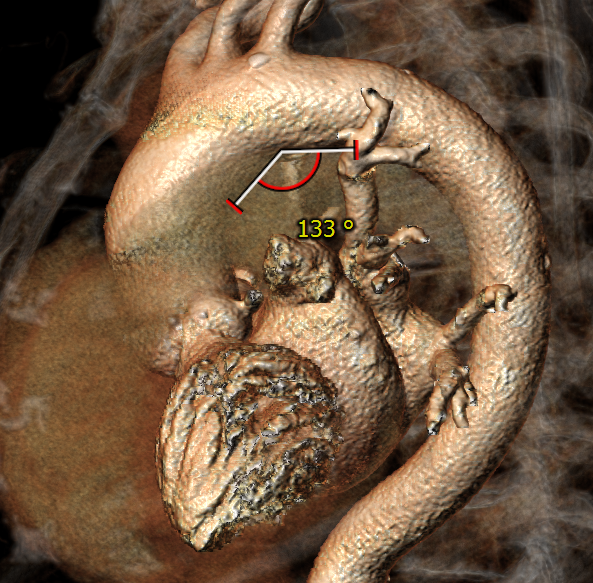

CT评估报告

瓣环平均直径:21.0 mm,左室流出道平均直径:22.6 mm

升主动脉未见明显扩张,心脏角度:46°

左冠高度:13.1 mm,瓣叶长度:18.0 mm;右冠高度:16.7 mm,瓣叶长度:17.3 mm

心腔较小,心肌较厚,主动脉弓部角度平缓

术前CT测量与冠脉风险评估